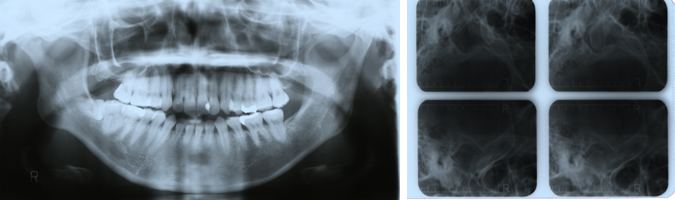

パノラマX線写真 顎関節規格X線写真

筋電図 下顎運動検査